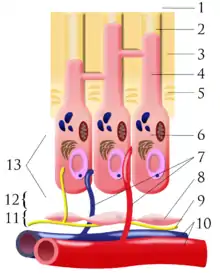

A tooth is composed of an outer shell of calcified hard tissues (from hardest to softest: enamel, dentin, and cementum), and an inner soft tissue core (the pulp system), which contains nerves and blood vessels. The visible parts of the teeth in the mouth – the crowns (covered by enamel) – are anchored into the bone by the roots (covered by cementum). Underneath the cementum and enamel layers, dentin forms the bulk of the tooth and surrounds the pulp system. The part of the pulp inside the crown is the pulp chamber, and the central soft tissue nutrient canals within each root are root canals, exiting through one or more holes at the root end (apical foramen/foramina). The periodontal ligament connects the roots to the bony socket. The gingiva covers the alveolar processes, the tooth-bearing arches of the jaws.[42]: 1–5

Enamel is not a vital tissue, as it lacks blood vessels, nerves, and living cells.[18] Consequently, pathologic processes involving only enamel, such as shallow cavities or cracks, tend to be painless.[18] Dentin contains many microscopic tubes containing fluid and the processes of odontoblast cells, which communicate with the pulp. Mechanical, osmotic, or other stimuli cause movement of this fluid, triggering nerves in the pulp (the "hydrodynamic theory" of pulp sensitivity).[19] Due to the close relationship between dentin and pulp, they are frequently considered together as the dentin-pulp complex.[43]: 118